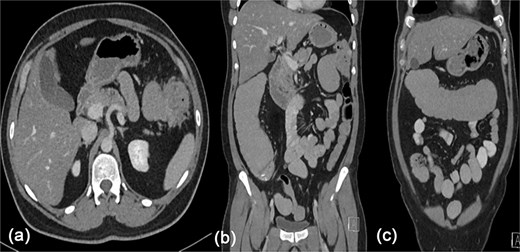

There was significant abdominal distention with mild tenderness during the physical examination, with an unremarkable digital rectal examination. The results of the lab tests were normal, but the computed tomography (CT) scan showed a mass invading the splenic flexure of the colon with an upstream dilation of the transverse colon, ascending colon, and small bowel (Fig. 1).

Contrast enhanced CT scan of the abdomen showing a heterogeneously enhancing lesion at the splenic flexure with upstream dilatation of the transverse and ascending colon.